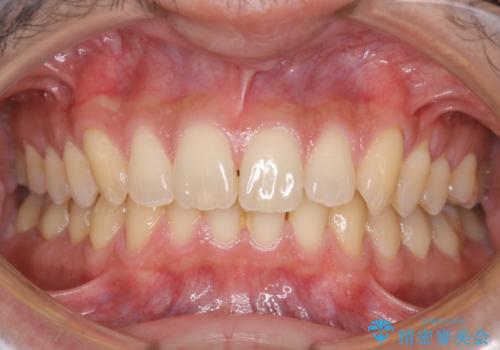

- 数年ぶりに歯科へ来院とのこと。全体的に歯のクリーニングをしてほしいとのことでした。

PMTC60分コースを行いました。

PMTCを行うことにより、スッキリと爽快感が得られたり、見た目も清潔感のある状態になるため、今後の治療などお口に対するモチベーションUPにも繋がります。